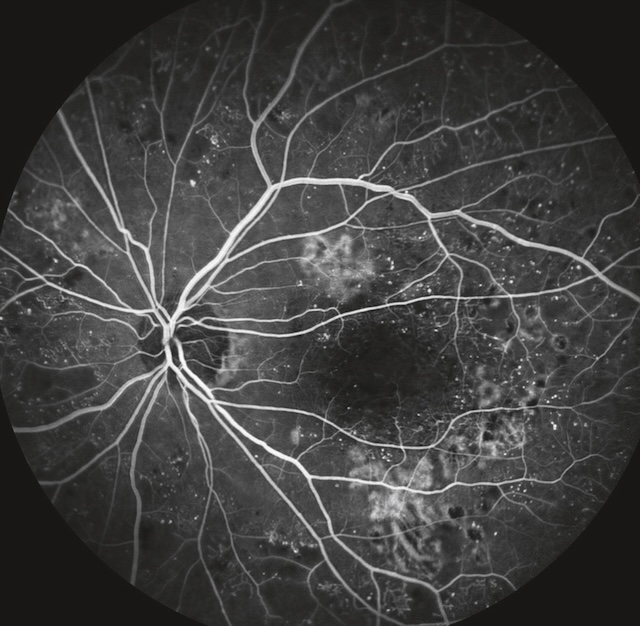

L’angiographie à la fluorescéine peut être un complément intéressant de l’examen et de la photographie du FO. Elle n’est pas demandée de façon systématique.

Elle facilite l’identification des territoires ischémiques périphériques et d’éventuels néovaisseaux; elle est également un support incontournable au traitement par photocoagulation au laser des œdèmes maculaires. Elle permet de déceler une hyperperméabilité capillaire (diffusion de colorant) et d’apprécier l’existence de territoires d’occlusion capillaire rétiniens. Elle évalue également le degré d’ischémie maculaire, même si l’OCT-angiographie tend à la supplanter.

Fig. 20.8 Angiographie à la fluorescéine d’une rétinopathie diabétique proliférante avec des néovaisseaux prérétiniens (laissant diffuser la fluorescéine) en bordure de territoires d’occlusion capillaire. Cette angiographie à la fluorescéine met en évidence une rétinopathie diabétique proliférante active. Au centre, de vastes zones d’occlusion capillaire apparaissent comme des régions sombres, sans perfusion, traduisant une ischémie rétinienne sévère. En périphérie de ces zones, on observe des néovaisseaux prérétiniens hyperfluorescents, brillamment marqués par une fuite de fluorescéine, soulignant leur activité. Ces néovaisseaux, fins et anarchiques, émergent à proximité des territoires ischémiques, selon le schéma typique de la réponse vasoproliférative à l’hypoxie rétinienne. L’image illustre un stade avancé nécessitant une prise en charge urgente.